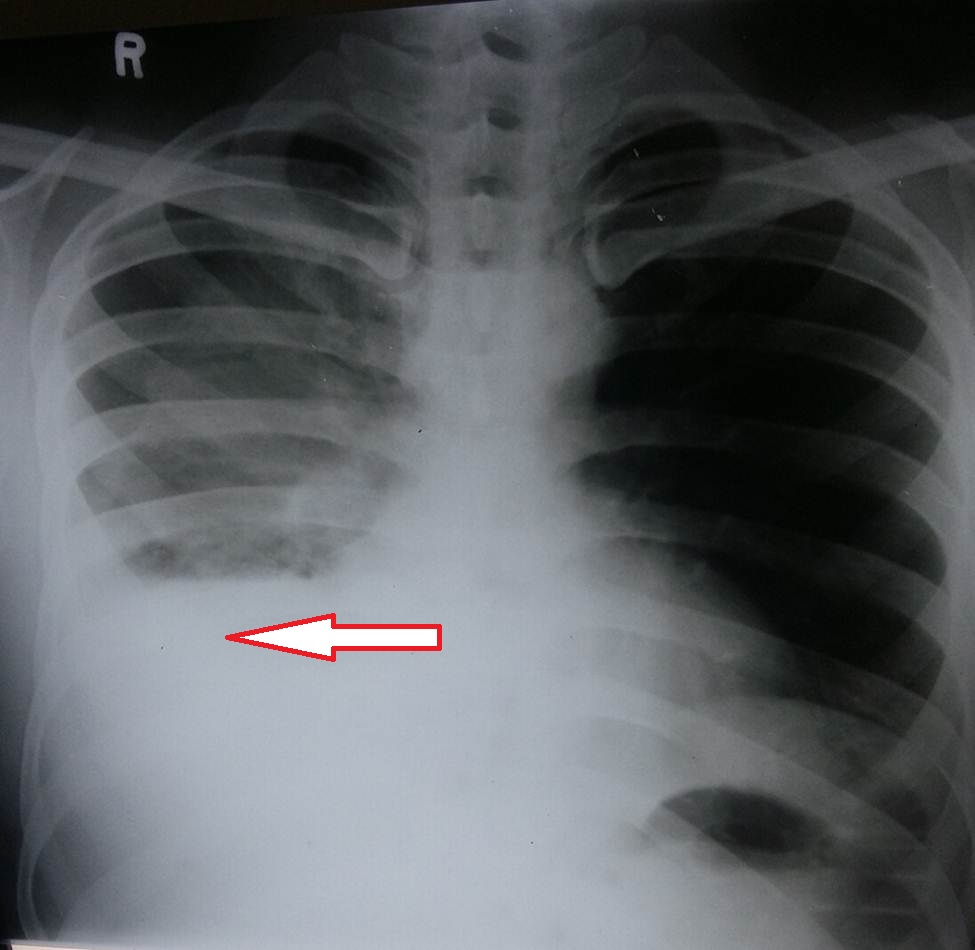

- Figure 3. Right upper lobe mass